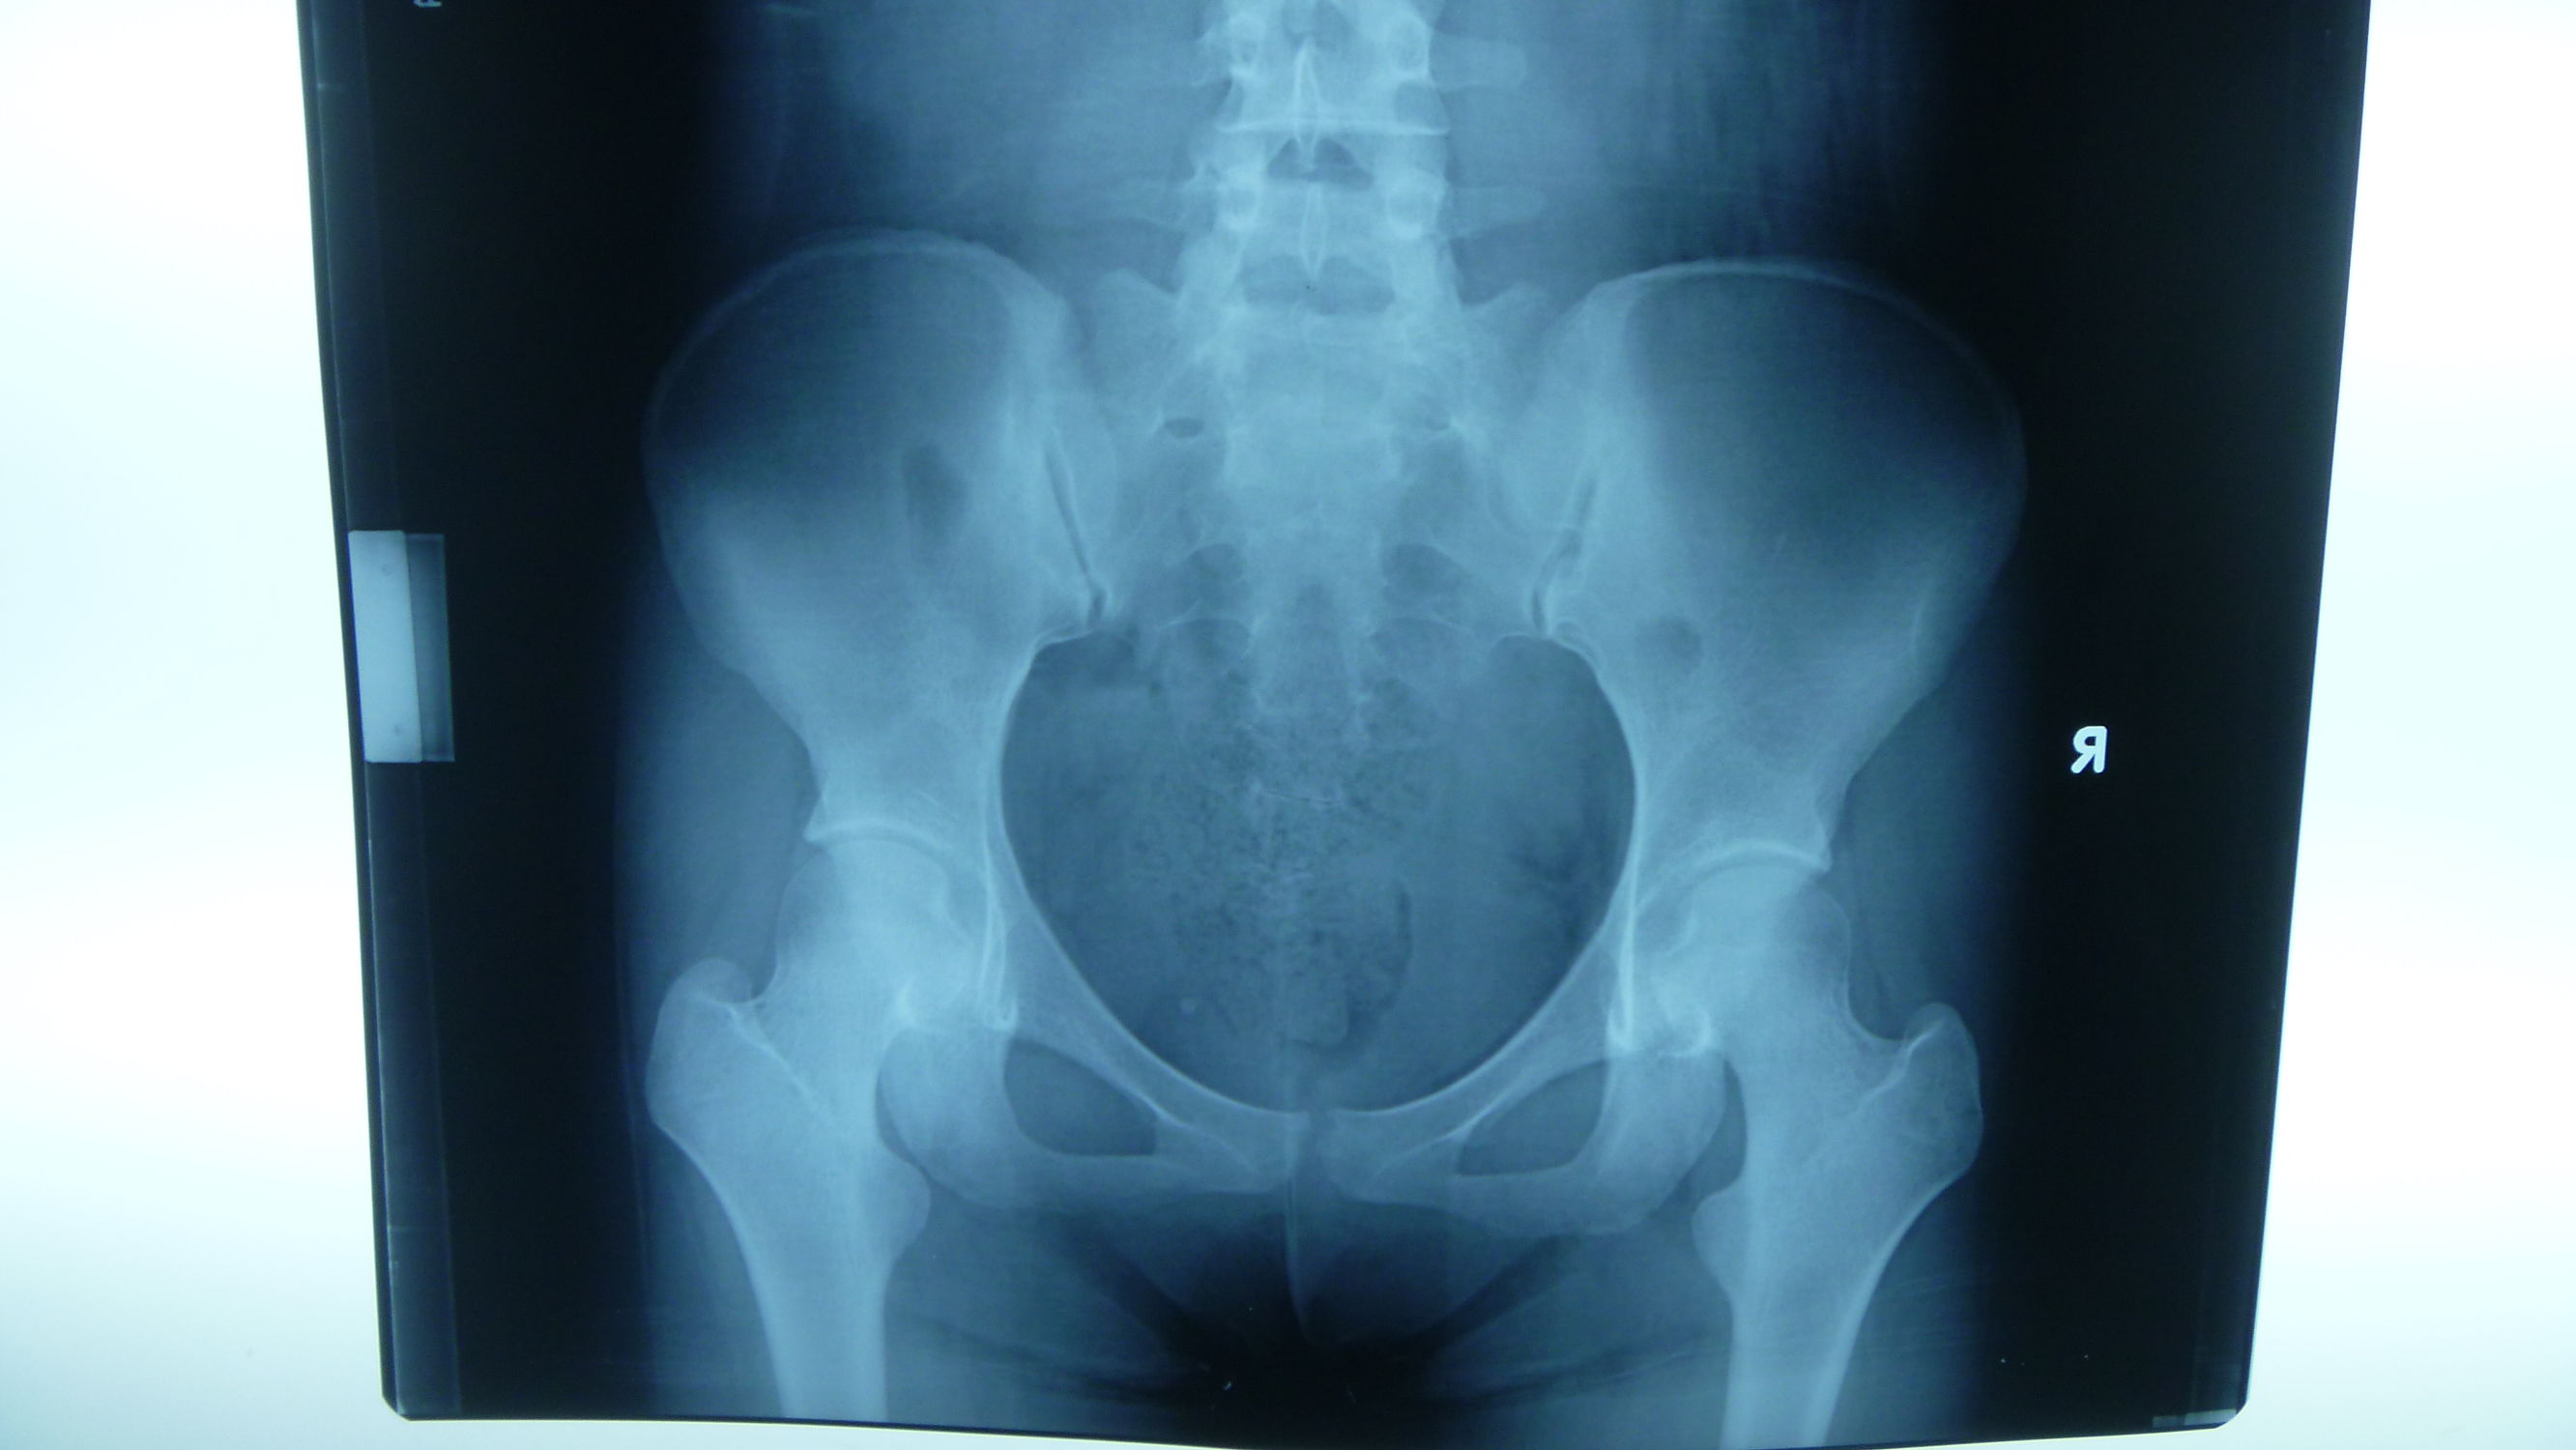

37周胎心监护、测胎心率、测量盆骨,决定分娩方式

胎心的正常范围是多少?正常胎心率为120~160次/分钟。怀孕20周前胎心率平均为160次/分钟。怀孕21~30周平均为147次/分钟。怀孕31~40孕周平均为139次/分钟。

在家中家庭监测胎心的方法:听诊器、胎心仪、胎语仪。准备胎心仪,心情平稳的情况下,平躺,胎心声是如钟表的“嗒嗒声”,在腹部同一位置,缓慢持续加压。如在这一位置没有听到,以与这一位置半径5厘米转移。